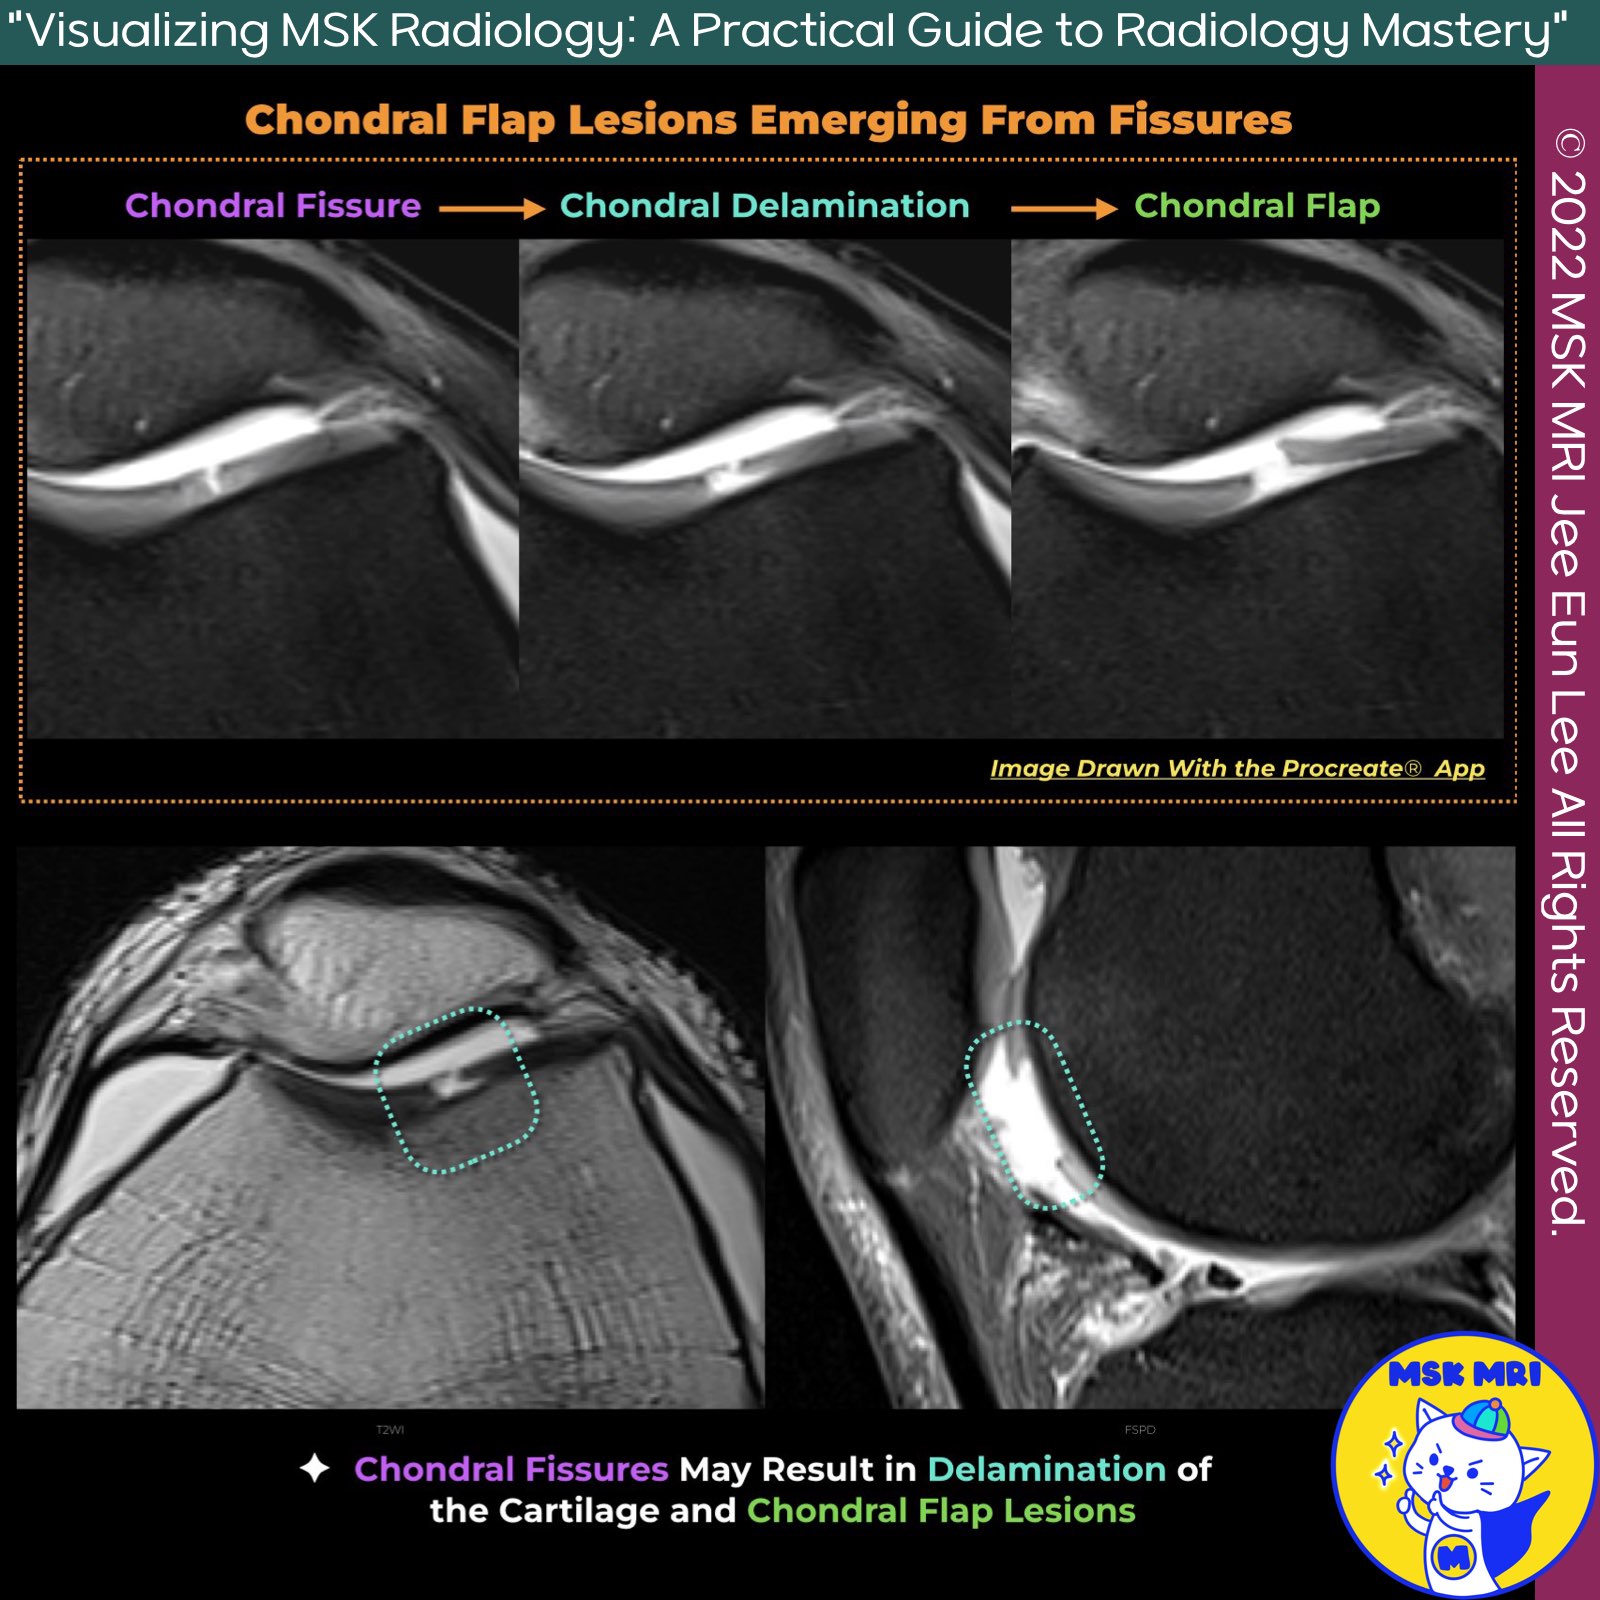

📌 Fissure with Chondral Flap

✅ Chondral Fissures and Delamination

- Chondral fissures may result in delamination of the cartilage and chondral flap lesions if there is extension of the fissure parallel to the surface of the bone.

- MRI Appearance of Chondral Delamination: With MRI, chondral delamination usually appears as a thin line of near-fluid signal intensity beneath the deep zone of articular cartilage, at the tidemark, separating the noncalcified cartilage from the underlying bone and calcified cartilage.

✅ Transverse Region of Failure

- A transversely oriented region of failure in the midzone of articular cartilage is sometimes seen in association with chondral fissures on MRI.

- The transversely-oriented region of failure that is sometimes seen in the midzone of articular cartilage may represent delamination between pathologically disorganized collagen fibers.